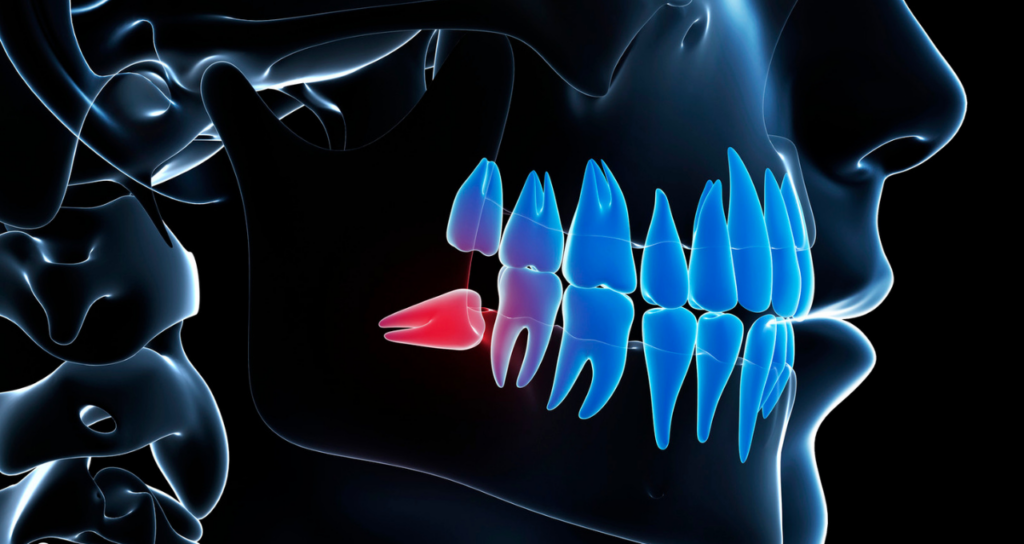

親知らず(第三大臼歯)は、前歯から数えて8番目にある一番奥の歯です。

10代後半から20代前半頃に生えてくることが多いため、親が知らない間に生えることからその名がついたと言われています。

現代人は顎が小さくなっている傾向があり、親知らずが正常に生えるためのスペースが不足しているケースが大半です。その結果、斜めに生えたり横を向いて埋まっていたりして、様々なトラブルを引き起こします。

口腔外科認定医による「難症例」への対応

親知らずの抜歯は、歯科治療の中でも特に技術と経験を要する処置の一つです。

特に、歯茎の中に深く埋まっている「完全埋伏智歯」や神経の近くに根があるケースは、一般的な歯科医院では対応が難しく大学病院へ紹介されることが少なくありません。